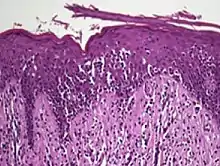

Diagnosis is sometimes difficult because the early phases of the disease often resemble inflammatory dermatoses (such as eczema, psoriasis, lichenoid dermatoses including lichen planus, vitiligo, and chronic cutaneous lupus erythematosus), as well as other cutaneous lymphomas.[10] Several biopsies are recommended, to be more certain of the diagnosis.

The criteria for the disease are established on the skin biopsy:[11]

- the superficial papillary dermis is infiltrated by a bandlike lymphocyte infiltrate

- epidermotropism

- presence of atypical T-cells with cerebriform nuclei in the dermal and epidermal infiltrates.

Pautrier's microabcesses are aggregates of four or more atypical lymphocytes arranged in the epidermis.[12] Pautrier microabcesses are characteristic of mycosis fungoides but are generally absent.

Traditionally, mycosis fungoides has been divided into three stages: premycotic, mycotic and tumorous. The premycotic stage clinically presents as an erythematous (red), itchy, scaly lesion. Microscopic appearance is non-diagnostic and represented by chronic nonspecific dermatosis associated with psoriasiform changes in epidermis.

In the mycotic stage, infiltrative plaques appear and biopsy shows a polymorphous inflammatory infiltrate in the dermis that contains small numbers of frankly atypical lymphoid cells. These cells may line up individually along the epidermal basal layer. The latter finding if unaccompanied by spongiosis is highly suggestive of mycosis fungoides. In the tumorous stage a dense infiltrate of medium-sized lymphocytes with cerebriform nuclei expands the dermis.